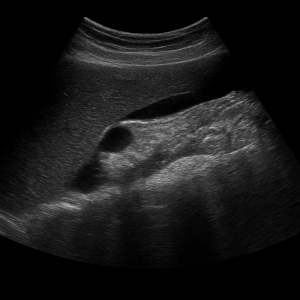

간은 복부초음파에서 가장 먼저 살펴보는 장기예요. 초음파로 지방간, 간경변, 결절, 낭종, 혈관종, 간암 등 여러 가지 변화를 감지할 수 있고, 간 기능 검사에 이상이 있을 때 특히 중요하게 확인해요.

담낭과 담관

담낭은 담석이나 담낭염, 담낭 벽 두께 변화 등을 확인하는 데 아주 유용하답니다. 담관의 확장이나 폐쇄 여부도 복부초음파로 간접적으로 알아볼 수 있어요.

간 질환

- 지방간

간에 기름이 쌓이면 초음파에서 밝고 반짝이는 모습으로 보일 수 있어요. 요즘 지방간이 흔한데, 초음파로 쉽게 확인되서 유용합니다. - 간경변

만성 염증으로 간이 딱딱해지고 울퉁불퉁해지는 상태예요. 초음파에서 간 표면이 거칠고 모양이 변형된 모습으로 나타나요. - 간암(간 종양)

덩어리나 혹처럼 생긴 이상이 초음파 화면에 포착될 수 있어요. 양성 종양인지 악성인지 구분하려면 추가 검사가 필요할 때도 있어요.